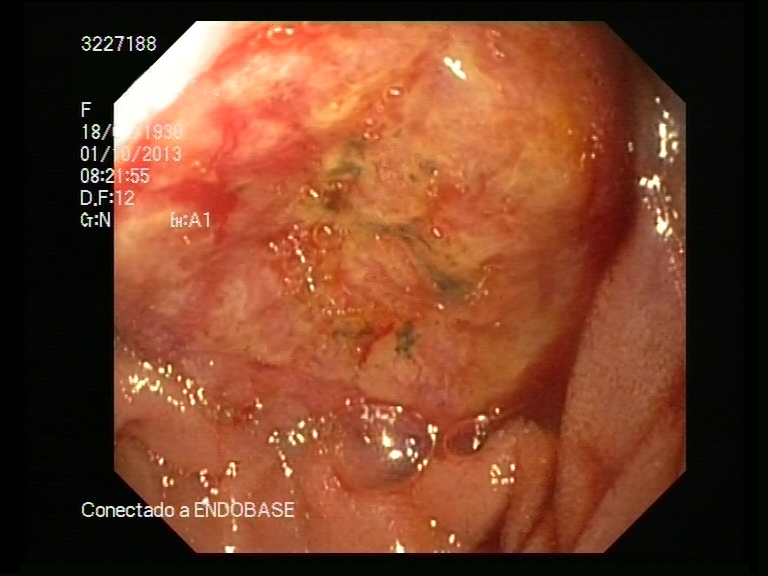

Metástasis intestinales yeyunales, forma de presentación de un carcinoma pulmonar

Los tumores primarios de intestino delgado son muy infrecuentes, siendo todavía más raros los metastásicos. Es excepcional que las metástasis de intestino delgado se manifiesten antes que el tumor primario. La presentación clínica puede requerir una resección quirúrgica intestinal motivada por perforación, hemorragia, obstrucción-suboclusión intestinal e incluso invaginación intestinal. La supervivencia, es escasa y generalmente no supera las 20 semanas, independientemente del tratamiento que se realice.